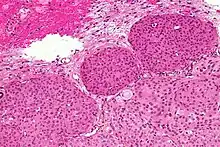

Micrograph of a meningioma showing the characteristic whorling, HPS stain

Micrograph of a meningioma with brain invasion (WHO Grade II). The tumour (bottom/right of image) has the typical "pushing border" invasion into the cerebral cortex (top/left of image), HPS stain.

Meningiomata arise from arachnoidal cap cells,[15] most of which are near the vicinity of the venous sinuses, and this is the site of greatest prevalence for meningioma formation. Some subtypes may arise from the pial cap cells that migrate during the development together with blood vessels into the brain parenchyma.[16] They most frequently are attached to the dura over the superior parasagittal surface of frontal and parietal lobes, along the sphenoid ridge, in the olfactory grooves, the sylvian region, superior cerebellum along the falx cerebri, cerebellopontine angle, and the spinal cord. The tumor is usually gray, well-circumscribed, and takes on the form of the space it occupies. They usually are dome-shaped, with the base lying on the dura.

Histologically, meningioma cells are relatively uniform, with a tendency to encircle one another, forming whorls and psammoma bodies (laminated calcific concretions).[17] As such, they also have a tendency to calcify and are highly vascularized.